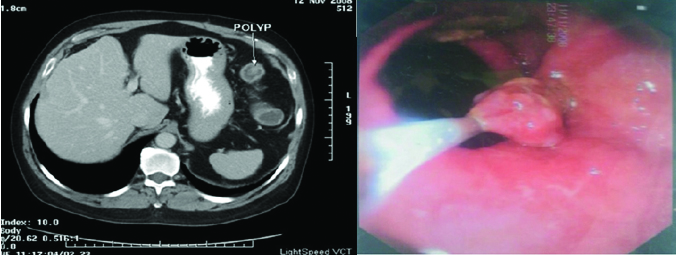

The study was more confined towards adults. Only five cases were less than 20 years of age and the youngest case of this study was 17-year-old. There were 27 females and rest 33 were males. Twelve patients were diagnosed having appendicitis using axial, MPR and curved MPR images. All of them were found having appendicitis on surgery [Table/Fig-1]. Twenty eight cases had inflammatory bowel disease out of which seven persons were diagnosed with intestinal Koch’s disease. For (non-neoplastic) inflammatory bowel diseases, following findings were considered: mild symmetrical wall thickening (<1.5 cm); segmental bowel wall thickening (>10 cm length of the involved bowel); homogeneous enhancement pattern with mural stratification and surrounding fat stranding, for neoplastic diseases marked asymmetrical wall thickening (>1.5-3.0 cm); focal bowel wall involvement (< 10 cm length of involvement); heterogeneous enhancement with associated enhancing lymph nodes or liver metastasis. Necrotic lymph nodes and/or loculated collections with peritonitis were considered for infective (e.g., Koch’s disease) aetiologies. Seven patients were put on ATT and were followed in six months. One case was lost in follow up and was excluded from the study. Out of the six remaining five patients, responded to ATT. One case did not respond to ATT, who then underwent colonoscopy. Colonoscopy revealed Crohn’s disease in it. Rest of the seventeen patients were reported to have findings of non-specific colitis and they responded well with antibiotic treatment. Four patients had idiopathic inflammatory bowel diseases. Three were reported as idiopathic inflammatory bowel disease (ulcerative colitis in two cases and Crohn’s disease in one). One patient was reported normal who subsequently underwent colonoscopy and was diagnosed with Crohn’s disease. Thus, one case was missed on CT. Three cases were reported as mesenteric ischemia (ischaemic colitis) and vascular occlusion. They subsequently underwent triple phase study which confirmed thrombus in Superior Mesenteric Artery (SMA) in first case [Table/Fig-2], thrombus in segmental branch of SMA in second case and thrombus in SMV in the third case [Table/Fig-3,4]. The overall sensitivity of MDCT for diagnosing inflammatory bowel is 96.3% and the specificity is 100%. Two cases were noted with secondary signs of perforation which include free fluid and free air in peritoneal cavity. There bowel findings revealed perforation in jejunum in one case and perforation in ileum in the other. The same was confirmed on surgery. In three cases, findings were suggestive of bowel malignancy. In one case growth was seen at recto-sigmoid junction and in two cases growth was seen at hepatic flexure of colon [Table/Fig-5]. They underwent colonoscopy and out of three cases, all the three cases revealed mitotic growth. This group included patients with findings which included hernias, diverticula and polyps. The same was confirmed on either surgery or on colonoscopy [Table/Fig-6]. The sensitivity, specificity, positive predictive value, negative predictive value and the kappa statistics for all the cases are given in [Table/Fig-7].

CT axial image showing a colonic polyp. Same was confirmed on colonoscopy.

The overall sensitivity of MDCT for diagnosing inflammatory bowel is 96.3% and the specificity is 100%. Three cases were reported as mesenteric ischemia (ischaemic colitis) and vascular occlusion. They subsequently underwent triple phase study which confirmed thrombus in SMA in first case, thrombus in segmental branch of SMA in second case and thrombus in SMV in the third case. Our results were consistent with the study done earlier by Mazzeo S et al., [10]. The sensitivity of MDCT in diagnosing bowel perforation in our study was 100% which is almost consistent with the study done by Hainaux B et al., [11]. In three cases findings were suggestive of malignancy one was seen which growth at recto-sigmoid junction and two were seen with mass growth at hepatic flexure of colon. They underwent colonoscopy and out of three cases, two revealed mitotic growth. One was diagnosed with inflammatory thickening. However, our study varies mildly compared to early studies may be due to less number of cases. Sixteen patients had findings which included hernias, diverticula and polyps. The same was confirmed on either surgery or on colonoscopy, thus sensitivity and specificity of our study was 100% and 100% respectively.